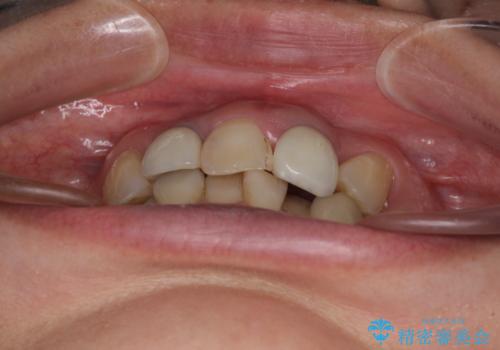

- 非対称な前歯や奥歯の目立つ銀歯を気にして来院された患者様です。

左上前から2番目の歯は、以前裏側に位置していたことから抜歯をされていましたが、前歯の非対称が長年気になっているとのことでした。

前歯の横幅が大きいことも気になっていたので、矯正治療で前歯5本の幅をコントロールしながら移動させ、治療開始前より一回りサイズの小さいセラミッククラウンを装着することができました。